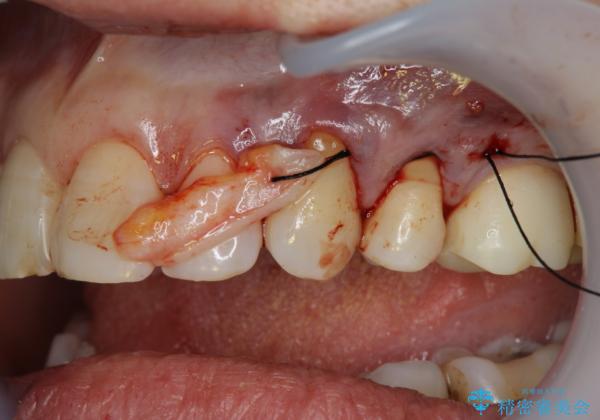

過度なブラッシング圧により歯が削れてしまい、歯ぐきの下がりも認められます。

改善を図るため、結合組織移植を行い歯ぐきの再生を計画します。